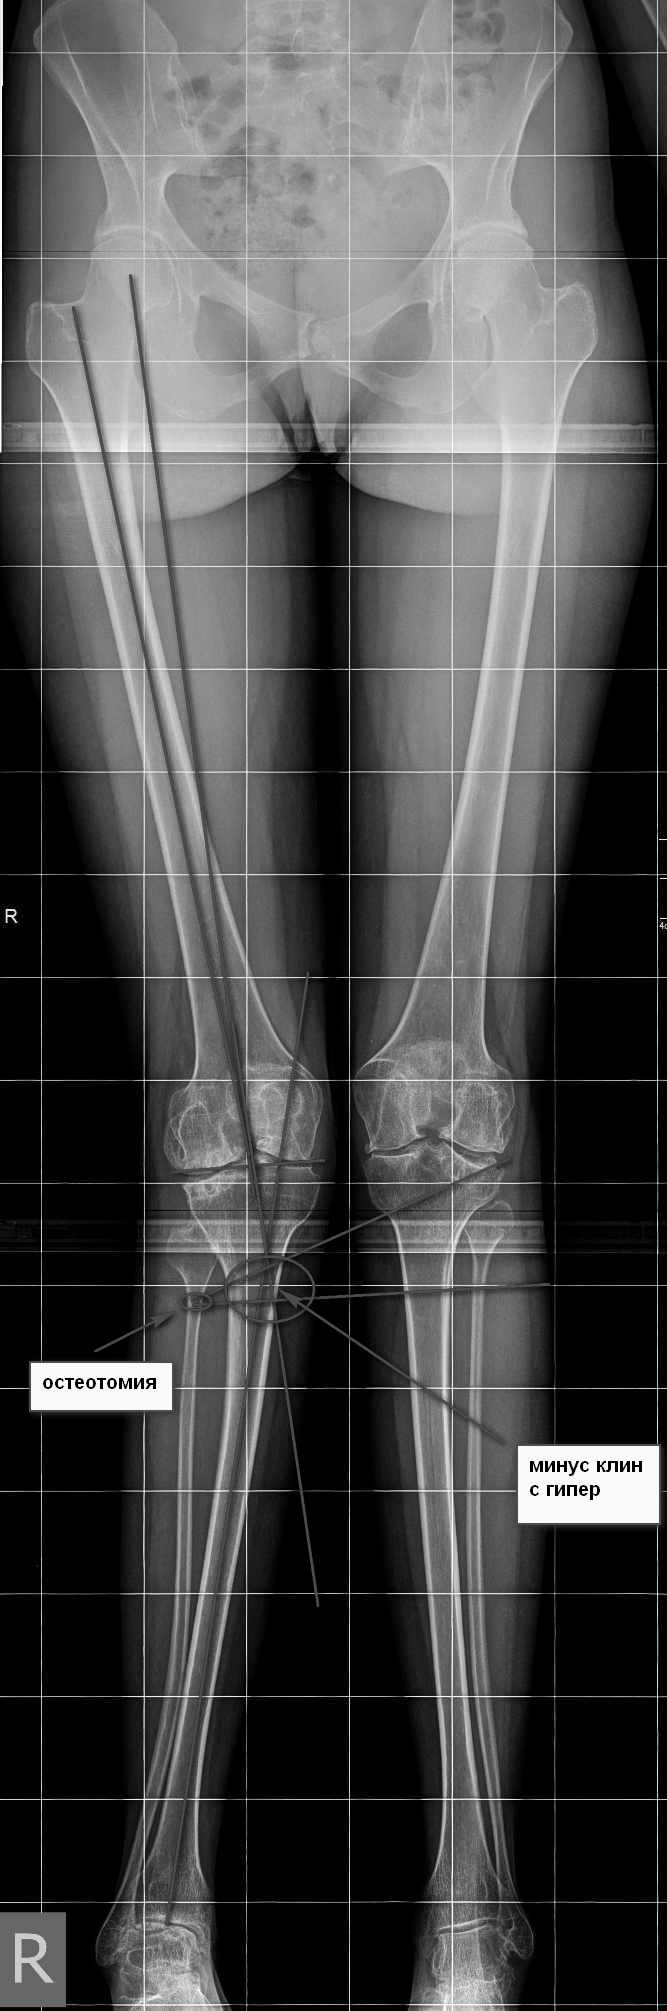

Имя     : GORODENSKAYA E-S-- 14-08-1987- CR from 17-02-2016 2 S1	I0.jpg

Тип     : image/jpeg

Размер  : 138456 байтов

Описание: отсутствует

Url     : http://weborto.net:8080/pipermail/ortho/attachments/20160920/04b75196/attachment-0007.jpg